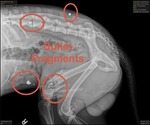

Dog Breed: Terrier / Mixed (medium coat). Forever Home Wanted: Meet Oso! Oso’s story could’ve gone sideways — he was found after being shot with BBs, and we braced ourselves for surgery. But Oso had other plans. No surgery needed — just a permanent little limp that he completely ignores. And honestly, that fits him perfectly, because Oso is all about enjoying life. He loves people, gets along great with other dogs, and moves through the world like nothing is going to slow him down. He’s also potty trained, which makes settling into a home that much easier. Oso does have a bit of a prey drive when it comes to small animals like chickens and rabbits, so a home without small pets would be the best fit for him. He’s happy, social, resilient, and incredibly easy to love. Limp and all, Oso is the kind of dog who reminds you that strength can come with a wagging tail and a joyful spirit. If Oso sounds like he could be the perfect fit for your home, fill out an application at .labradorsandfriends. Oso is located in Southern California.